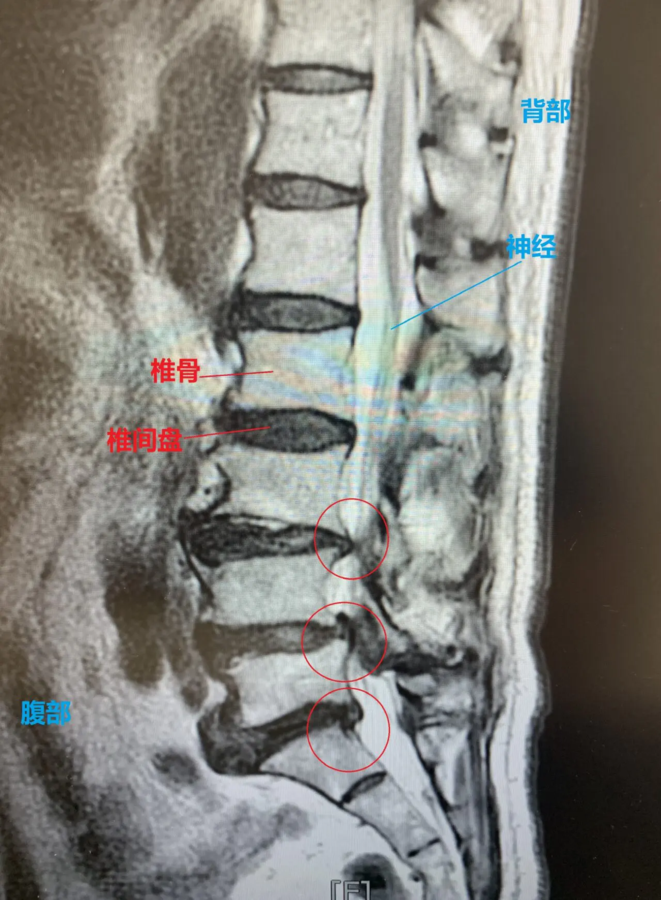

腰椎核磁影像显示多节椎间盘变形(椎间盘突出)。压迫支配腿的神经,伴有椎管狭窄症。

检查了怀疑损伤的三节椎间盘(L3/L4、L4/L5、L5/S)并进行了修复再生治疗。